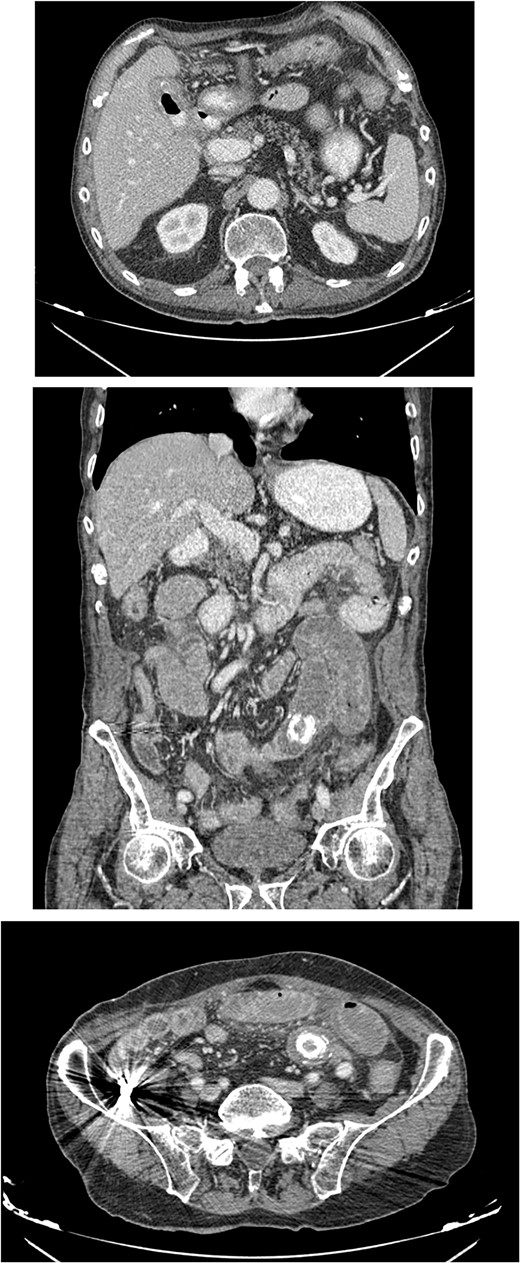

An 80-year-old male presented to the emergency department complaining of intermittent abdominal pain, vomiting and intense nausea beginning 3 days prior. The patient reported a medical history of type 2 diabetes mellitus, hypertension and coronary artery disease. Upon arrival, he was afebrile (T: 37°C) and tachypneic (24 breaths/minute), the following vital signs were: heart rate 98 bpm, blood pressure 160/95 mmHg, oxygen saturation 96%. Examination of the abdomen revealed significant hypoactive bowel sounds and diffuse tenderness. Laboratory investigations revealed a white blood cell count of 8.190/mm3, hemoglobin of 15.9 g/dl, and elevated levels of C - reactive protein of 15.94 mg/dl (N < 0.5 mg/dl) whereas the rest of the laboratory parameters were within normal limits. The patient initially underwent plain chest and abdomen radiographs which revealed small bowel gas-fluid levels indicating intestinal obstruction and intravenous fluids resuscitation was initiated. A CT scan with IV and oral contrast which was later performed revealed gastric, duodenal and small bowel loops distension and swelling caused by a high attenuation mass within the intestinal lumen at the jejunum-ileum transition which was attributed to a gallstone. Α second possible gallstone of smaller diameter was located in jejunum loops, and a cholecysto-duodenal fistula, of air and oral contrast in the gallbladder, pneumobilia, and intraperitoneal fluid in Douglas’s pouch were also present (Fig. 3).

CT images with oral and IV contrast revealed presence of air and oral contrast in the gallbladder and small bowel obstruction caused by a mass in the jejunum–ileum transition attributed to a gallstone.